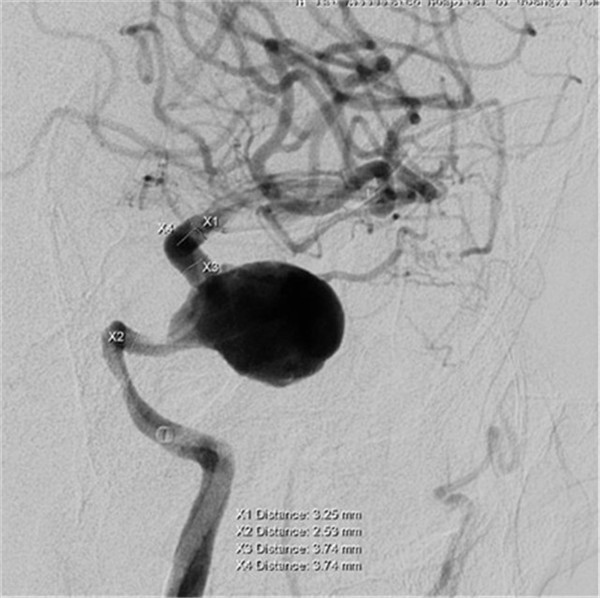

患者是一位70岁的女性,已视物重影1年余,经外院检查确诊为“左侧颈内动脉海绵窦段巨大动脉瘤伴瘤内血栓形成”,医生告知因动脉瘤位于海绵窦内,瘤颈宽约8mm,大小约2.8×2.3×2.2cm,传统手术方法无法完成动脉瘤夹闭或栓塞治疗,同时手术创伤大、风险高。听了医生的话患者不得不放弃手术。

最近,患者因症状加重来到YABO鸭脖第一附属医院求治。该院神经外科张高炼主任主持的治疗团队对该病例进行了讨论和分析,因影像学检查显示动脉瘤载瘤动脉明显迂曲且血管直径较细小,覆膜支架系统通过可能较困难且易引起载瘤血管损伤或动脉瘤破裂出血,他们决定利用密网支架技术行颅内巨大动脉瘤封堵技术为患者治疗。新技术的开展经汇报后得到院领导的大力支持,医院为此简化医疗药械申购手续,购买由美国eV3公司生产的Pipeline血流导向装置(密网支架系统),并邀请到中美合作上海德济医院院长宋冬雷教授前来会诊和指导。

术前DSA